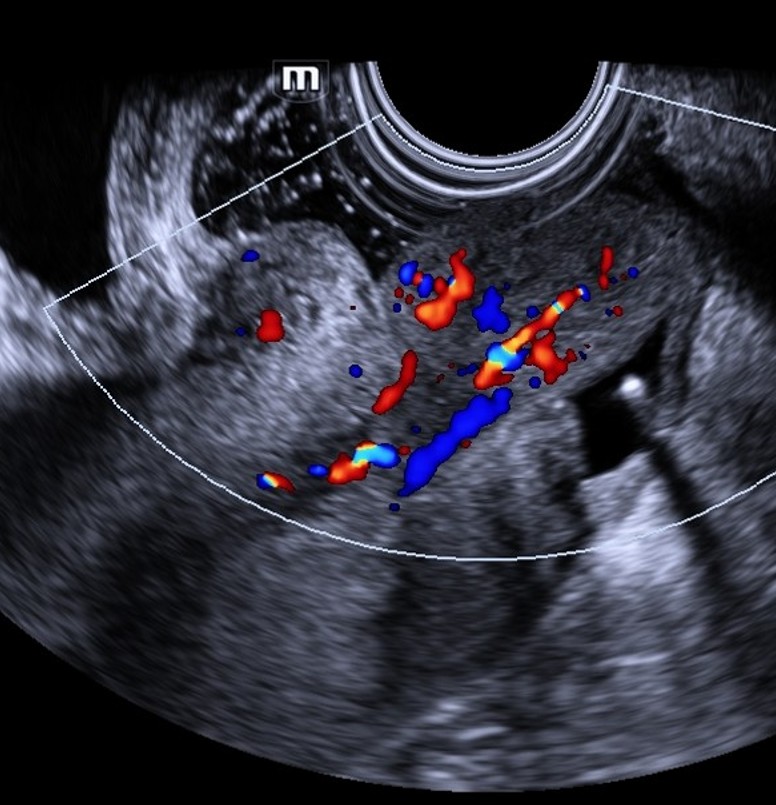

mioma_parido_gel

Ultrassonografia transvaginal com Doppler colorido. Observa-se formação sólida intracavitária, heterogênea, com pedículo vascular identificado ao Doppler, exteriorizando-se através do canal cervical. Achados compatíveis com mioma submucoso pediculado em processo de exteriorização (mioma parido).